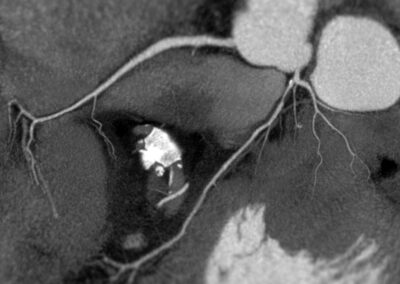

Τρισδιάστατη και δισδιάστατη απεικόνιση των στεφανιαίων αγγείων όπου διακρίνεται σημαντική στένωση λίγο μετά την έκφυσή του πρόσθιου κατιόντα κλάδου